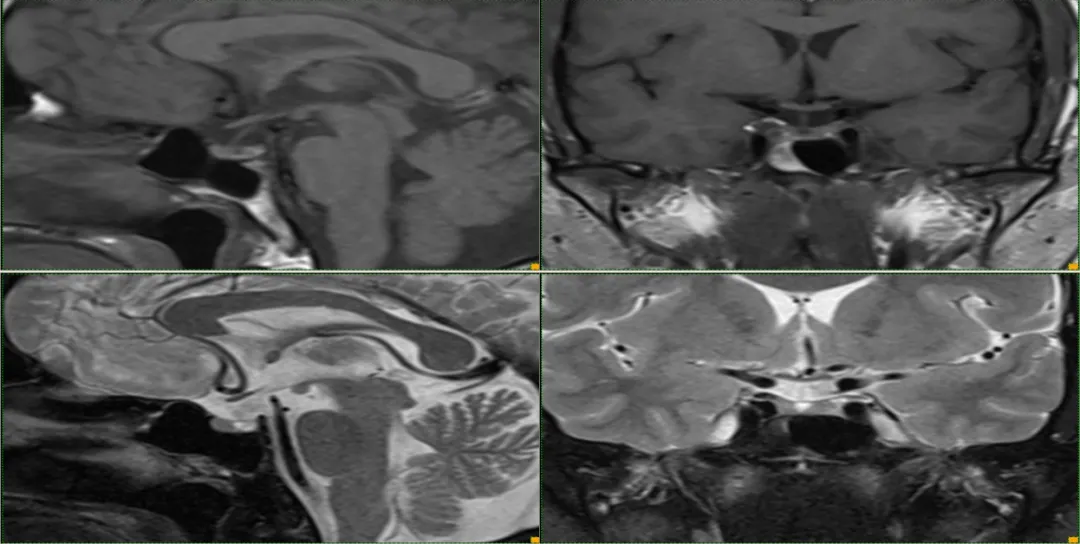

case 1: f/63y 头痛

T1WI 示垂体内高信号病变,增强无强化,左侧鞍旁脑膜瘤

case 2: f/46y24042 头痛

等 T1WI、等 T2WI 伴内低信号结节

case 3: f/34y 头晕 2 天入院,既往植物神经功能紊乱病史 2 年

T1WI 高 T2WI 低信号病变

case 4: M53Y,急性起病, 间断头痛 3 天

矢状位 T2WI 示:高信号囊肿和其内低信号结节

case 5:m/52y

T1WI 示垂体内高信号病变,位于正常 T1WI 高信号的神经垂体前方